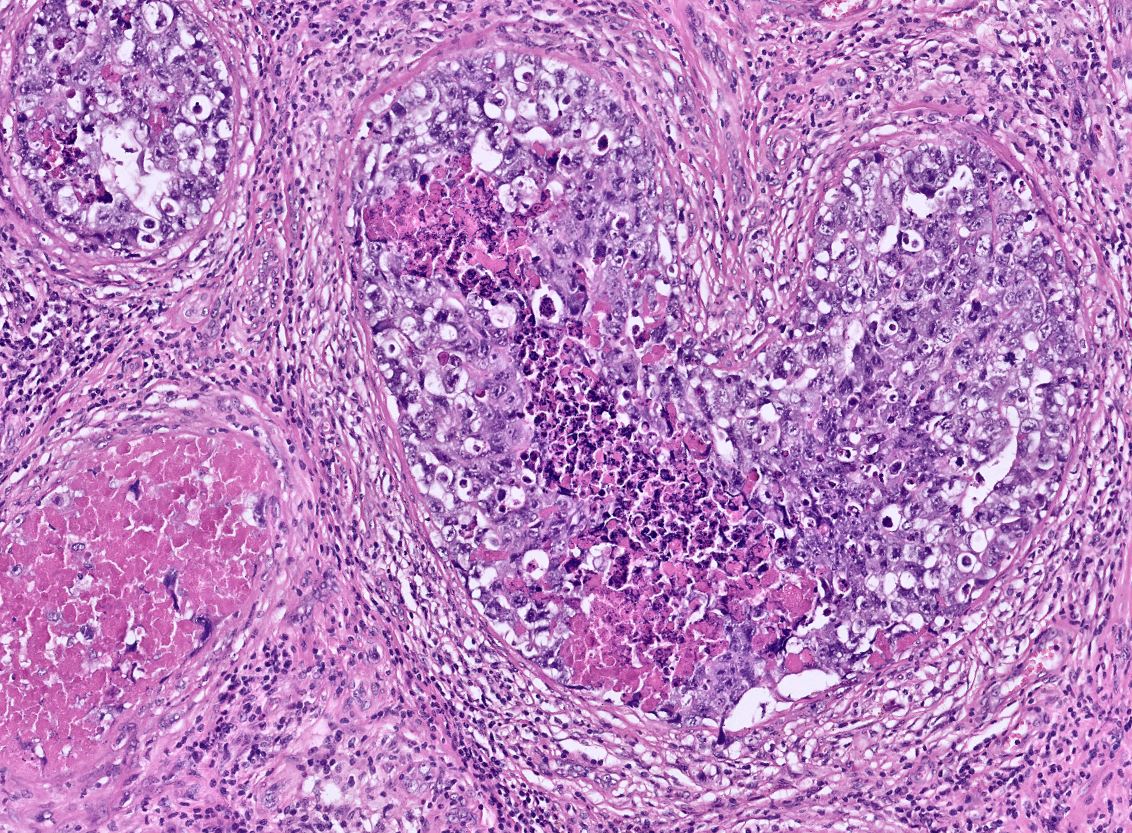

Radical orchidectomy Intratubular embryonal carcinoma with necrosis (in images) There was adjacent mixed germ cell tumour including embryonal carcinoma #PathTwitter #Pathology #PathResidents #GUPath

DrLaurenceGalea's tweet image. Radical orchidectomy

Intratubular embryonal carcinoma with necrosis (in images)

There was adjacent mixed germ cell tumour including embryonal carcinoma

#PathTwitter #Pathology #PathResidents #GUPath